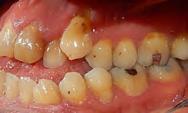

del caso donde podemos observar una enfermedad periodontal agresiva, con gran componente de pérdida

En las Figuras 2-27 se muestra uno de los casos incluidos en el estudio donde se situaron 4 de los implantes que forman parte de la muestra, por lo que hemos creído que era uno de los más representativos.

Figura 2. Imagen radiográfica inicial ósea en la mayoría de los dientes, con un defecto horizontal predominante y varios defectos en cuña en dientes aislados. Figura 3-6. Imágenes de la paciente, portadora de una prótesis removible para las ausencias dentarias presentes, que como vemos se encuentra completamente desadaptada además de con una estética poco adecuada.

2 3 5 7 4 6